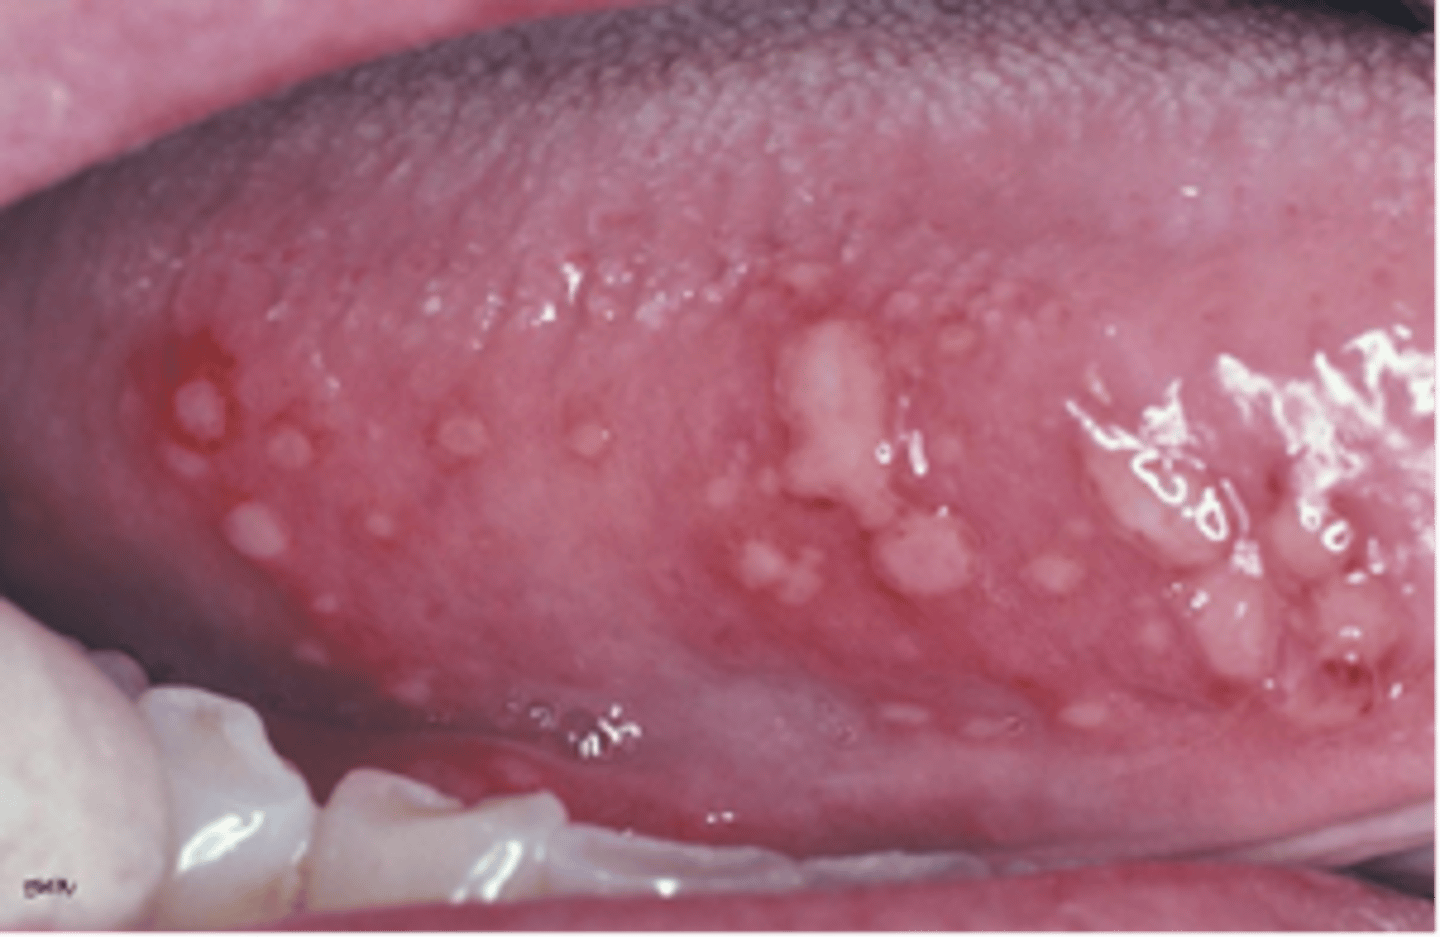

Picture of the bottom of the tongue with multiple white lesions. Stated that the patient had complaint of sore gums and tongue, he had a fever of 101 degrees.Most likely diagnosis?

- Primary Herpetic Stomatitis

- Secondary Herpetic Stomatitis

- Herpangia

- Recurrent Apthous Stomatitis

primary herpetic stomatitis

-treat with palliative care

What is the treatment for primary herpetic stomatitis?

- antibiotics

- palliative

- do nothing

- antifungals

palliative care